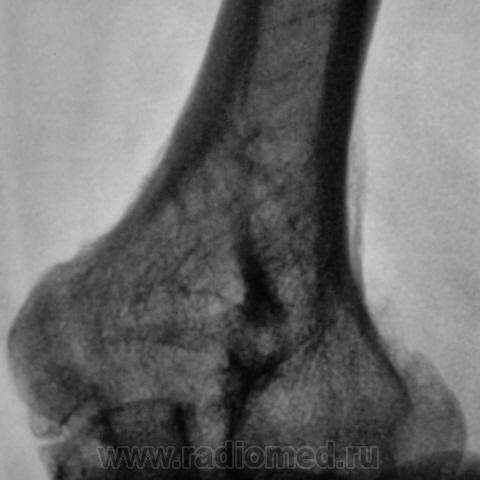

Пациент направлен на рентгенографию локтевого сустава. Была травма или не была не помнит. Пациент весьма пьющий, направлен хирургом с диагнозом "перелом". Рука в локтевом суставе полность не разгибается.

Ваше мнение уважаемые коллеги?

Наверно, застарелый перелом в области блока плечевой кости. Не понятен периостит.